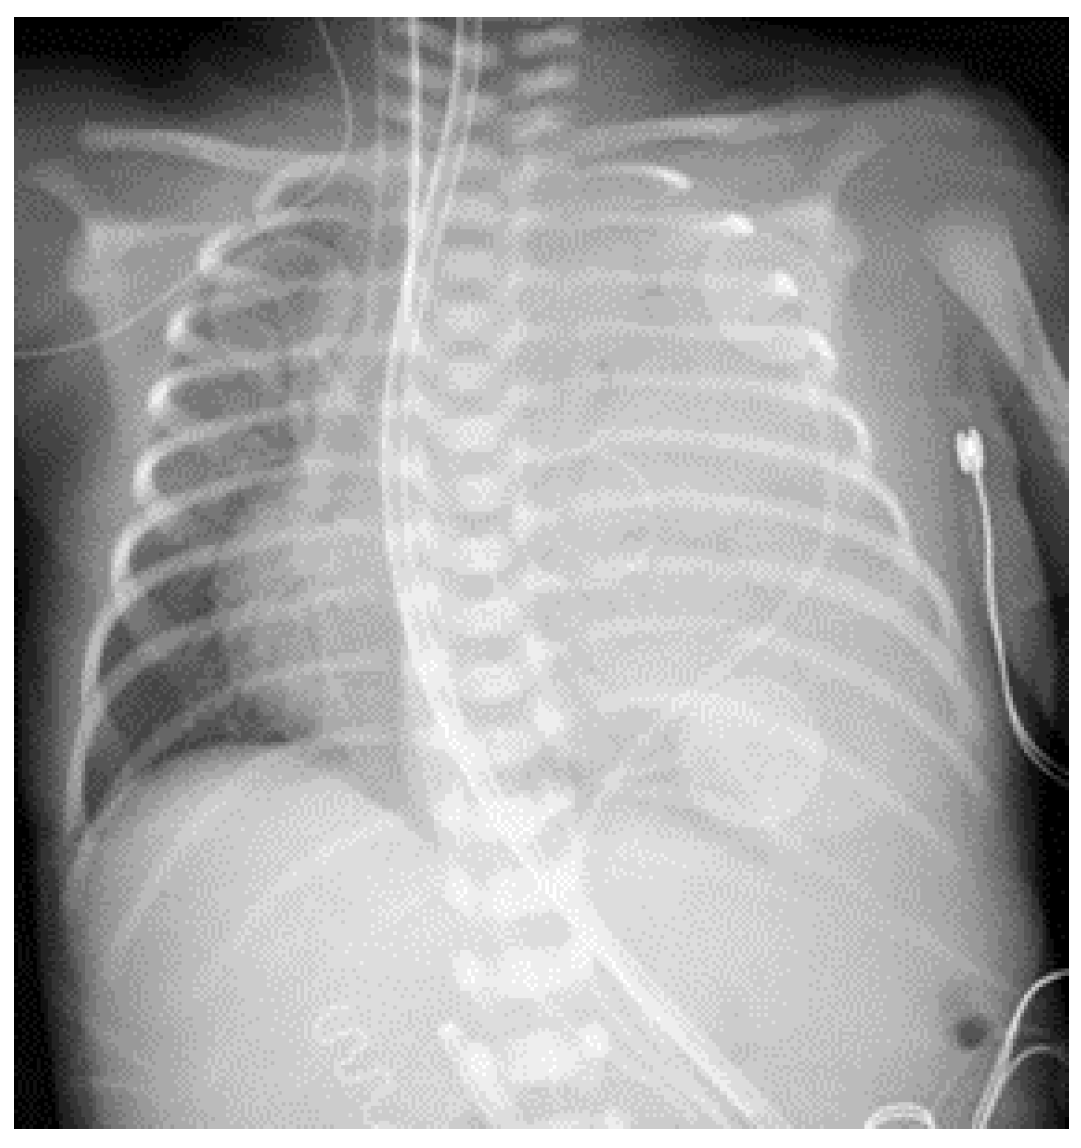

2. Case Presentation